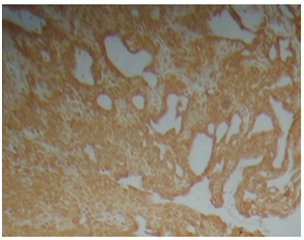

Craniopharyngioma are histologically a benign neoplasm that occurs in the sellar and suprasellar region, with an infiltrative growth pattern, accounts for 1.2-4.6% of all intracranial tumors.1 They are the most common non-neuroepithelial intracerebral neoplasm in children accounting for 5-10% of intracranial tumors in this age group. A bimodal age distribution of ACP is observed, with peaks in children aged 5-15years and adults 45-60years.1 They are often difficult to excise surgically, and they have a 10% to 40% recurrence rate.2 There are at two types of craniopharyngioma: Adamantinomatous craniopharyngioma (ACP) and papillary craniopharyngioma (PCP). Both have distinct morphology and different clinical behavior. ACP has at least four different squamous histological areas: superficial mature squamous (SMS), loosely cohesive aggregates of squamous cells known as “stellate reticulum” (SR), palisaded basal columnar (PBC) cells and nodules of wet keratin (WK) (Figure 1, Figure 2 & Figure 3). Cystic cavities containing squamous debris are lined by flattened epithelium. PCP occurs virtually exclusively in adults with mean age of 40-50years.3,4 Histologically, it is different from ACP by lacking nuclear palisading, wet keratin, and dystrophic calcification.5

Figure 3 Basal squamous layer, stellate reticulum and superficial squamous layer.